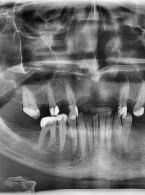

Przypadek pourazowej przyszyjkowej resorpcji zewnętrznej w zębie siecznym górnym przyśrodkowym u 15-letniego pacjenta

Zobacz więcej

Opublikowano dnia : 03.04.2025